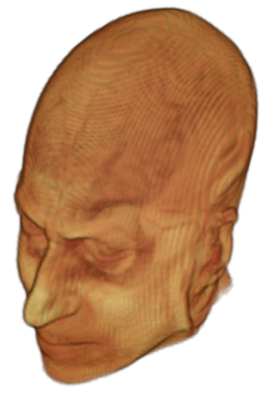

The digitalization of heath records has increased the risk of –and impact of– large scale data leaks. Although data compliance standards have been enacted to protect health records (HIPAA and GDPR), privacy of medical data is a growing concern. Three-dimensional scans such as magnetic resonance images (MRI) and computed tomography (CT), for example, contain an intrinsic privacy risk [Lotan et al.(2020)Lotan, Tschider, Sodickson, Caplan, Bruno, Zhang, and Lui]. Detailed renderings of the head can be crafted from 3D scans using techniques such as volumetric raycasting, as in Figure 1. This vulnerability can expose the patient’s identity if the renderings are matched to a face database [Mazura et al.(2012)Mazura, Juluru, Chen, Morgan, John, and Siegel, Lotan et al.(2020)Lotan, Tschider, Sodickson, Caplan, Bruno, Zhang, and Lui].

![]() |

Therefore, in this work, we define a new class of de-identification techniques that remodels the privacy-sensitive regions without altering the content of medically relevant data (see Figure 1). Under such a remodeling approach, the face, eyes, oral and nasal cavities, etc. should exhibit realistic appearance and structure of appropriate size, but should otherwise be independent of the original data. To solve this task, we propose a novel model called Convex Privacy GAN, or CP-GAN, that conditions on a convex hull of the skull extracted from the scan to be de-identified. The generator learns to synthesize volumes that preserve medically-sensitive regions such as the brain, while non-invertibly remodeling privacy-sensitive characteristics from the original scan.